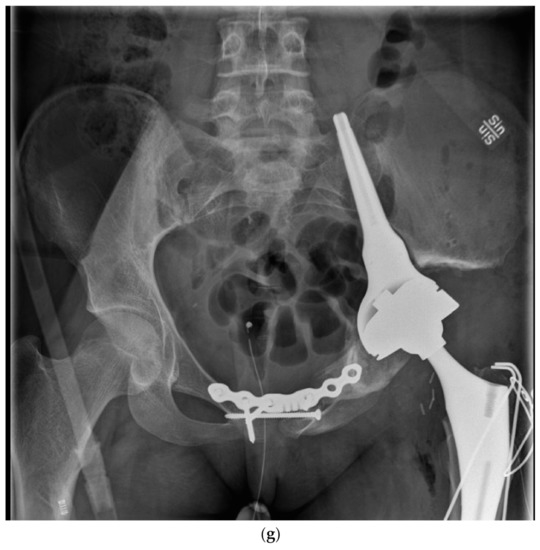

Figure 1.

Biological reconstruction using the bone transport technique (a) A two-year old girl presented to the emergency department unable to walk on her left leg after a mild fall 3 days earlier. She also had a fever and a c-reactive protein count of 87 mg/liter. X-ray showing a lytic lesion located centrally in the distal tibial metaphysis of the left leg. There is a relatively narrow, but indistinct zone of transition. Periosteal reaction involving the medial aspect of the tibia was observed. Open biopsy showed a dense proliferation of small round blue cells in hematoxylin and eosin. Immunohistochemistry showed membranous positivity for the CD99 marker; staining was also positive for S-100 and periodic acid–Schiff (PAS). Fluorescent in situ hybridization (FISH) demonstrated an EWSR1-FLI1 fusion transcript consistent with the diagnosis of Ewing sarcoma. Staging procedures did not show any metastases. (b) Induction chemotherapy with VIDE (vincristine, ifosfamide, doxorubicin, and etoposide) was given according to the Euro-Ewing 2008 protocol. Thereafter, physeal distraction, tumor resection, and segmental bone transport with the use of the Taylor Spatial Frame were carried out. The external fixator was removed after 6 months. (c) Five years after removal of the external fixator, the girl is pain free and is able to run and walk without any limitations. Two deformity procedures have been performed after completing oncologic treatment due to a varus deformity secondary to a physeal arrest in the distal tibial physis. She has no evidence of disease.